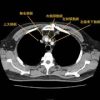

胸部外科

52 胸部外科疾病7